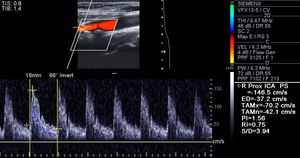

3. 2. 경동맥 죽상경화증

해부학적 감지 방법의 예로는 CT에 의한 관상 동맥 칼슘 점수, 초음파에 의한 경동맥 IMT(내막 중막 두께) 측정, 혈관내 초음파 (IVUS) 및 혈관내 광학 간섭 단층 촬영 (OCT)과 같은 혈관내 영상 기술이 있으며, 이를 통해 죽상 경화 플라크를 직접 시각화할 수 있다.[83][84]